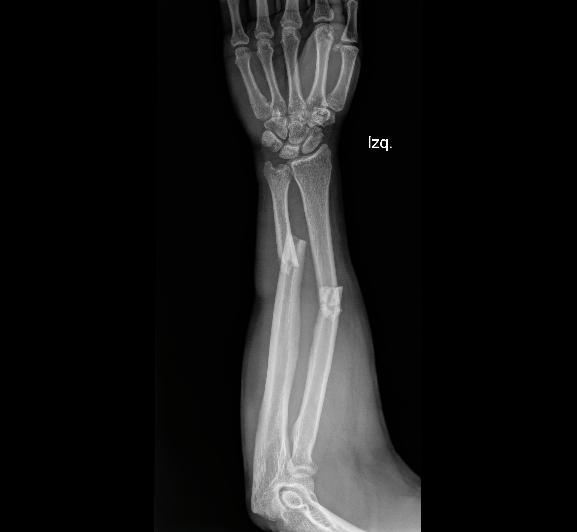

OSTEOSÍNTESIS

Paciente en postoperatorio de osteosíntesis de radio distal, que al inicio de la terapia presentaba marcada rigidez articular y limitación funcional. El proceso de rehabilitación convencional ha sido limitado, con solo dos sesiones de fisioterapia realizadas por EPS.

Las imágenes corresponden a la evolución a los dos meses de seguimiento, donde se documenta el estado funcional actual y los cambios observados pese a la baja frecuencia de terapia convencional.